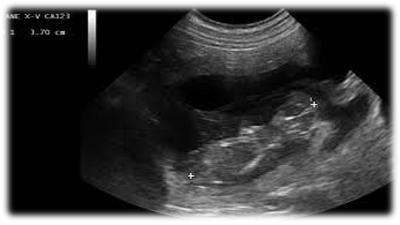

E' un'indagine diagnostica basata sulla risposta di un corpo al passaggio degli ultrasuoni. Gli ultrasuoni partono da una sonda attraversano il corpo e tornano a questa; la macchina, cioè l'ecografo, a questo punto trasforma segnali ricevuti in immagini che vanno dal nero, per un corpo a bassa densità, come un liquido, al bianco per un osso che ha maggior densità. Tra questi due estremi c'è una scala di tonalità di grigi, diversi a seconda dei vari organi. (...)

Da ciò si può capire che non sempre ecograficamente si possono apprezzare delle lesioni, inoltre certe volte alcune di esse hanno lo stesso colore dell'organo sano, quindi l'ecografista non riesce a vederle. Una lesione può quindi essere visualizzata se più bianca, cioè iperecogena, oppure più scura, cioè ipoecogena rispetto al tessuto sano. Per convenzione si parla di tessuto isoecogeno, cioè una tonalità di grigio che sta a metà tra bianco e nero, per la corticale del rene, tutto quello che è più chiaro o più scuro si valuta in confronto a questo e quindi si può stabilire se sano o patologico.

L'ecografia, quindi, presenta dei limiti; è, comunque, una grande metodica di indagine perchè rispecchia esattamente l'anatomia. Con molta probabilità chi non ha dimestichezza specifica vede solo un disegno confuso in bianco e nero, un po' come quei giochi della settimana enigmistica che sono inaccessibili finché non scopri la chiave di lettura, poi diventano evidenti, così l'ecografia quando hai la chiave di lettura diventa più semplice.